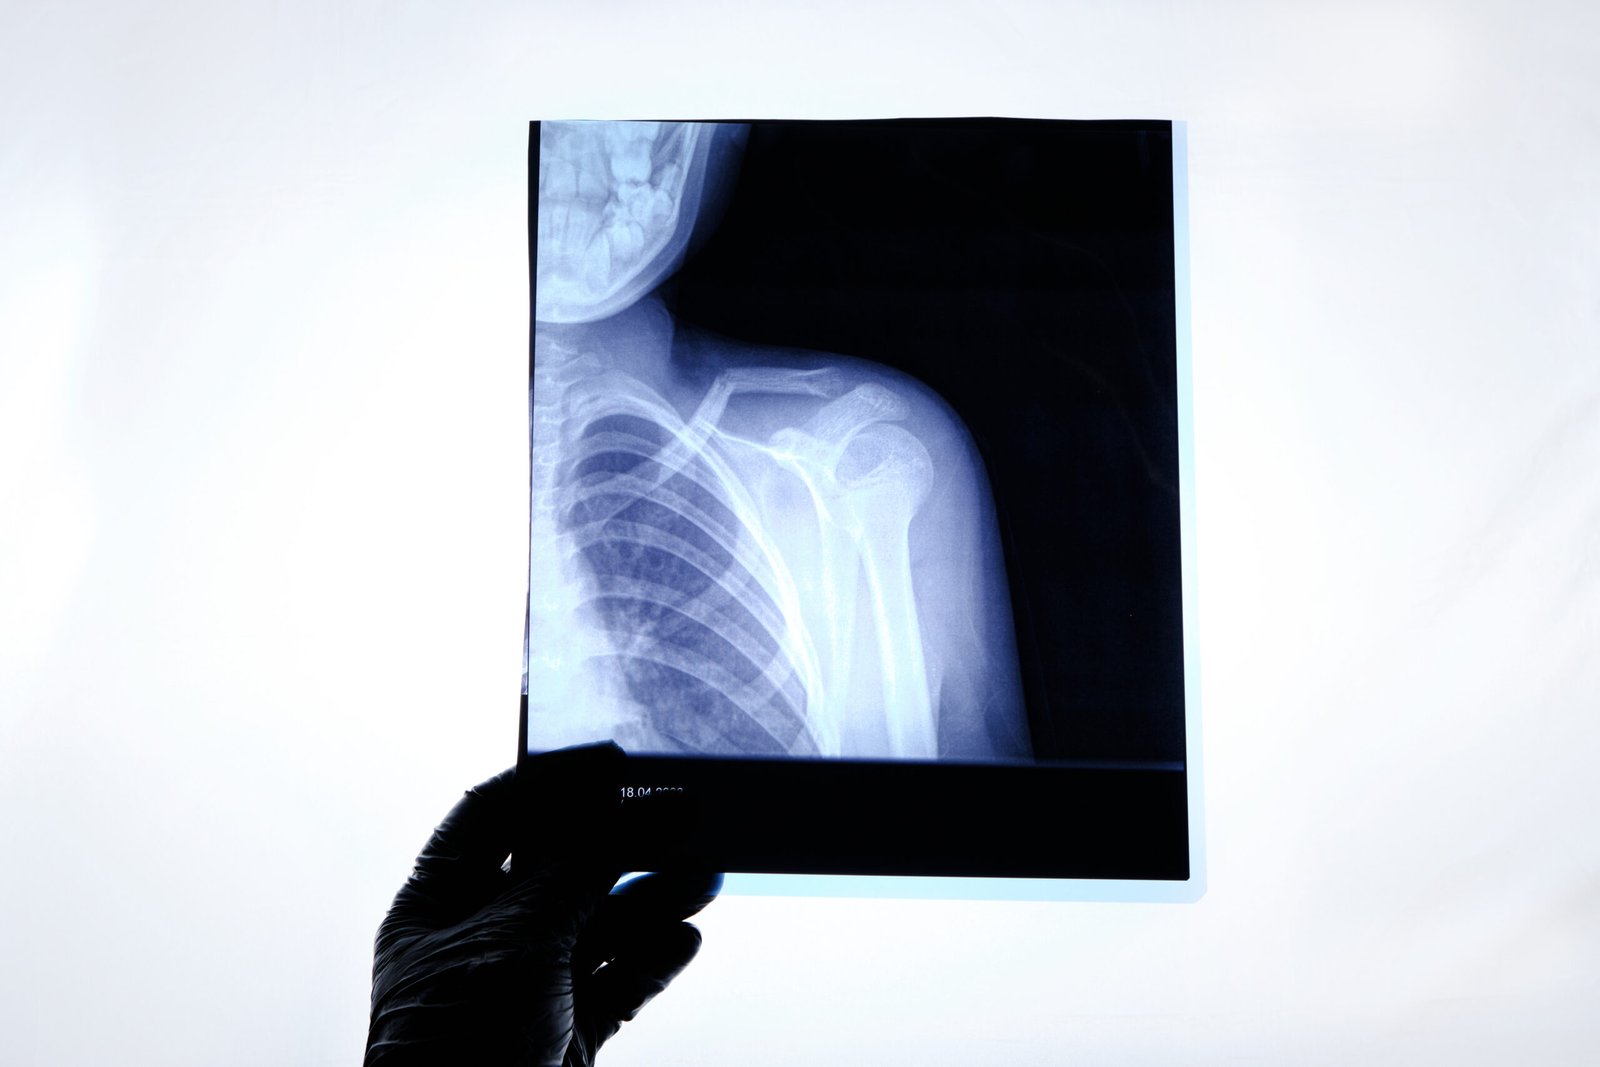

Understanding Shoulder Anatomy

Diagnosis of Shoulder Pain

The causes of shoulder pain may include a rotator cuff injury, a frozen shoulder, bursitis, tendinitis, a labral tear, and arthritis. It is also caused by overuse, trauma, poor posture, and repetitive motion. An accurate diagnosis is essential to identify the cause and implement the correct non-surgical treatment plan.